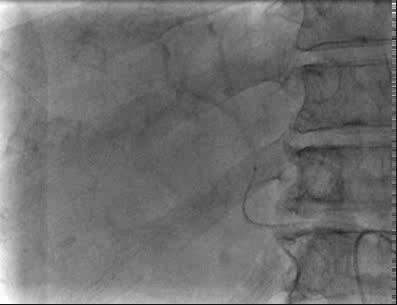

手术过程

术中造影发现肿瘤巨大,染色明显,微导管超选至其中几支肿瘤供血动脉后,予表柔比星80mg+聚乙烯醇栓塞微球(蓝色型,100-300um)、5支无色型(300-500um),1支无色型(500-700um)栓塞肿瘤供血动脉,直到栓塞至肿瘤血管血流停滞。